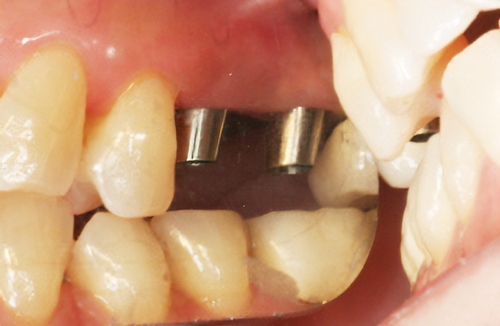

• 術前

土台

• 術後

術後